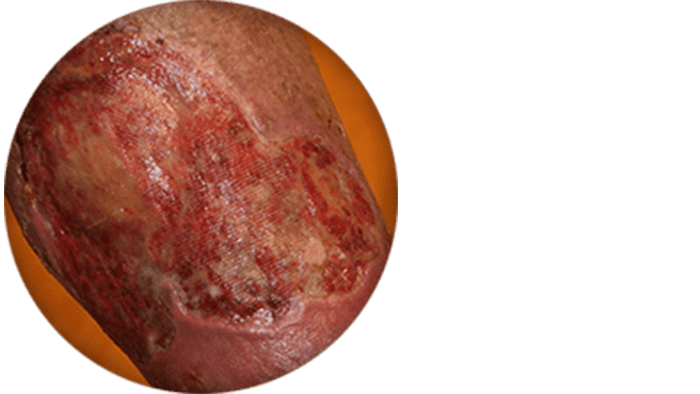

Ulcers

In severe cases, ulcers may develop when pooled blood causes tissue damage.

Swelling, skin changes, and ulcer images courtesy of Dr. Raghu Kolluri.